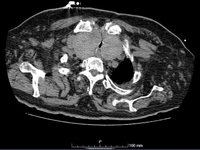

Cintilografia de tireoide mostrando captação variegada no bócio multinodular tóxico

Cortesia da Dra. Elizabeth Pearce; usado com permissão